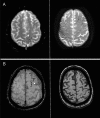

Objective: To assess the association of cortical superficial siderosis (cSS) presence and extent with future bleeding risk in cerebral amyloid angiopathy (CAA).

Methods: This was a meta-analysis of clinical cohorts of symptomatic patients with CAA who had T2*-MRI at baseline and clinical follow-up for future intracerebral hemorrhage (ICH). We pooled data in a 2-stage meta-analysis using random effects models. Covariate-adjusted hazard ratios (adjHR) from multivariable Cox proportional hazard models were used.

Results: We included data from 6 eligible studies (n = 1,239). cSS pooled prevalence was 34% (95% confidence interval [CI] 26%-41%; I 2 87.94%; p < 0.001): focal cSS prevalence was 14% (95% CI 12%-16%; I 2 6.75%; p = 0.37), and disseminated cSS prevalence was 20% (95% CI 13%-26%; I 2 90.39%; p < 0.001). During a mean follow-up of 3.1 years (range 1-4 years), 162/1,239 patients experienced a symptomatic ICH-pooled incidence rate 6.9% per year (95% CI 3.9%-9.8% per year; I 2 83%; p < 0.001). ICH incidence rates per year according to cSS status were 3.9% (95% CI 1.7%-6.1%; I 2 70%; p = 0.018) for patients without cSS, 11.1% (95% CI 7%-15.2%; I 2 56.8%; p = 0.074) for cSS presence, 9.1% (95% CI 5.5%-12.8%; I 2 0%; p = 0.994) for focal cSS, and 12.5% (95% CI 5.3%-19.7%; I 2 73.2%; p = 0.011) for disseminated cSS. In adjusted pooled analysis, any cSS presence was independently associated with increased future ICH risk (adjHR 2.14; 95% CI 1.19-3.85; p < 0.0001). Focal cSS was linked with ICH risk (adjHR 2.11; 95% CI 1.31-2.41; p = 0.002), while disseminated cSS conferred the strongest bleeding risk (adjHR 4.28; 95% CI 2.91-6.30; p < 0.0001).

Conclusion: In patients with CAA, cSS presence and extent are the most important MRI prognostic risk factors for future ICH, likely useful in treatment planning.

Classification of evidence: This study provides Class III evidence that in symptomatic CAA survivors with baseline T2*-MRI, cSS (particularly if disseminated, i.e., affecting >3 sulci) increases the risk of future ICH.